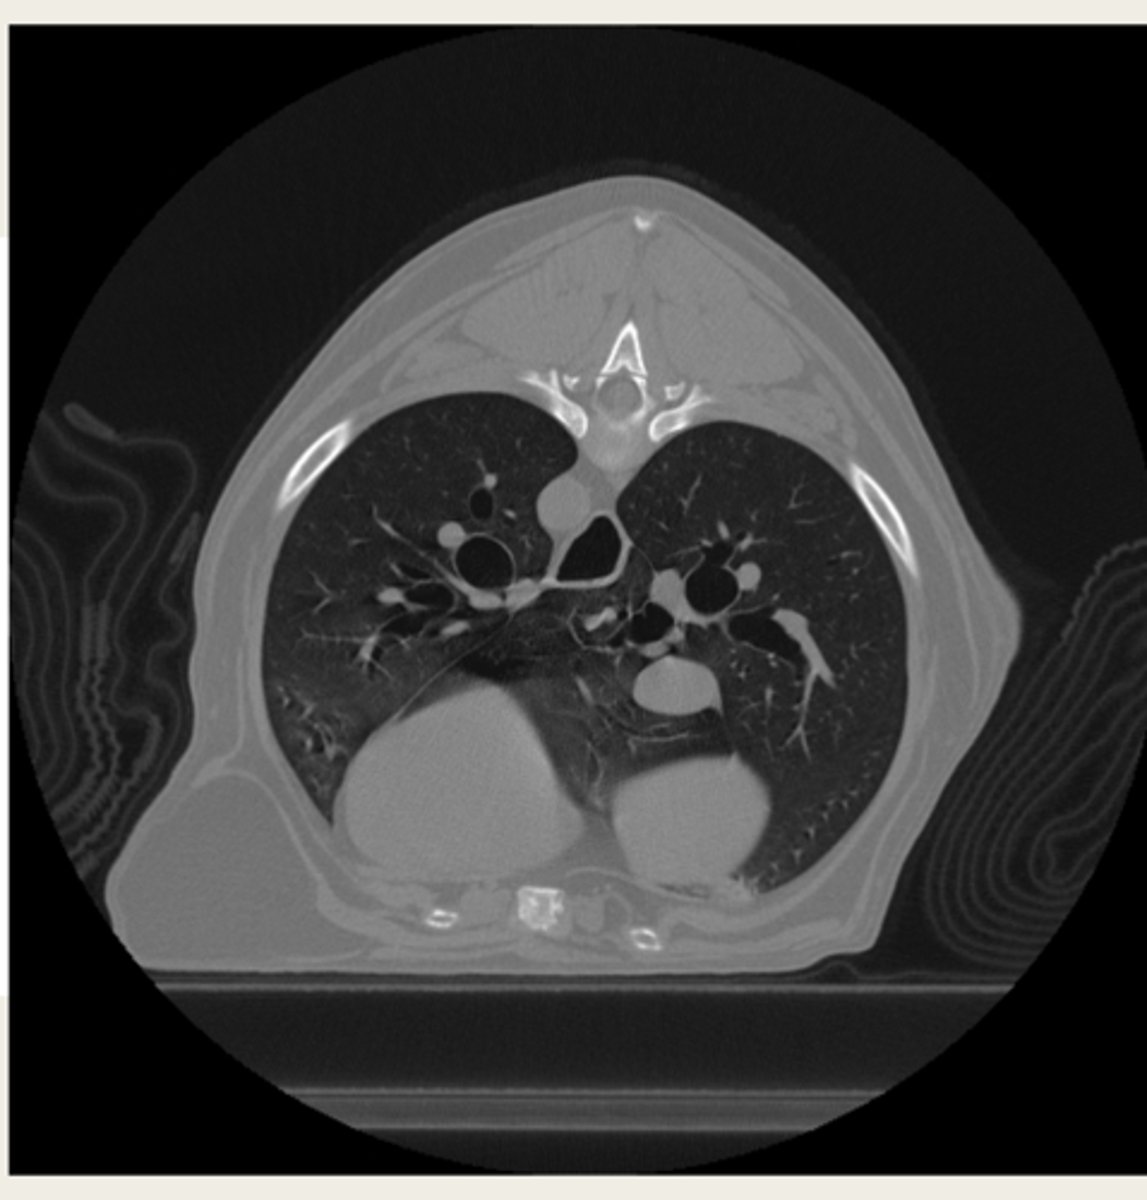

-lumps/bumps

-trauma

-lung disease

-nasal disease

-orbital masses

-bone disease

-IVDD

-abdominal disease

what are some CT indications?

should you do a CT or MRI for the thorax/metastasis?